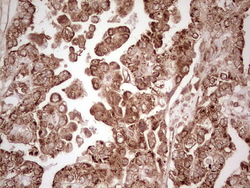

Supportive validation

- Submitted by

- OriGene (provider)

- Main image

- Experimental details

- Immunohistochemical staining of paraffin-embedded Adenocarcinoma of Human breast tissue using anti-WIBG mouse monoclonal antibody. (Heat-induced epitope retrieval by 1 mM EDTA in 10mM Tris, pH8.5, 120C for 3min, TA806496)

- Validation comment

- IHC